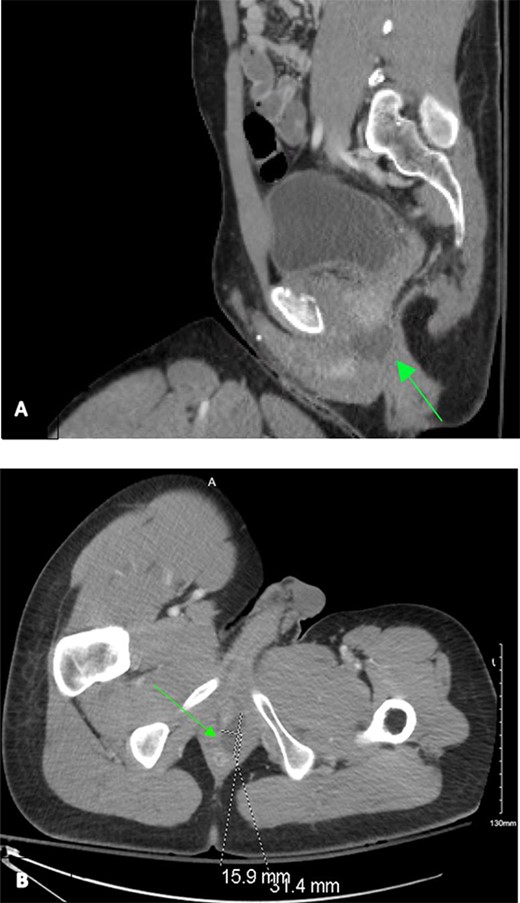

A 31-year-old African American man with history of schizophrenia and prior traumatic amputations of the left upper and left lower extremities was referred to the Emergency Department as a tier 2 trauma activation following a blunt injury in an auto versus pedestrian collision, where he was a wheelchair-bound pedestrian hit by oncoming traffic. On presentation, the primary survey was unremarkable and noted to be hemodynamically stable. Extended Focused Assessment with Sonography in Trauma exam showed no free fluid. Secondary survey was remarkable for pelvic tenderness. He endorsed diffuse midline cervical, thoracic, and lumbar tenderness with palpation. However, no step-offs, deformities, or external signs concerning for traumatic spinal cord injury were noted. Given the mechanism of injury, as well as the secondary exam findings, computed tomography (CT) of the chest, abdomen and pelvis was obtained. Imaging revealed a non-operative left superior ramus fracture and a 31 mm by 16 mm left homogenous cystic lesion, situated at base of the prostate and spanning from the anorectal junction to the urogenital sinus (Fig. 1).

Contrast-enhanced CT chest/abdomen/pelvis during a tier 2 trauma activation, revealing a homogenous hypodense perianal fluid collection from sagittal (A) and transverse (B) planes.